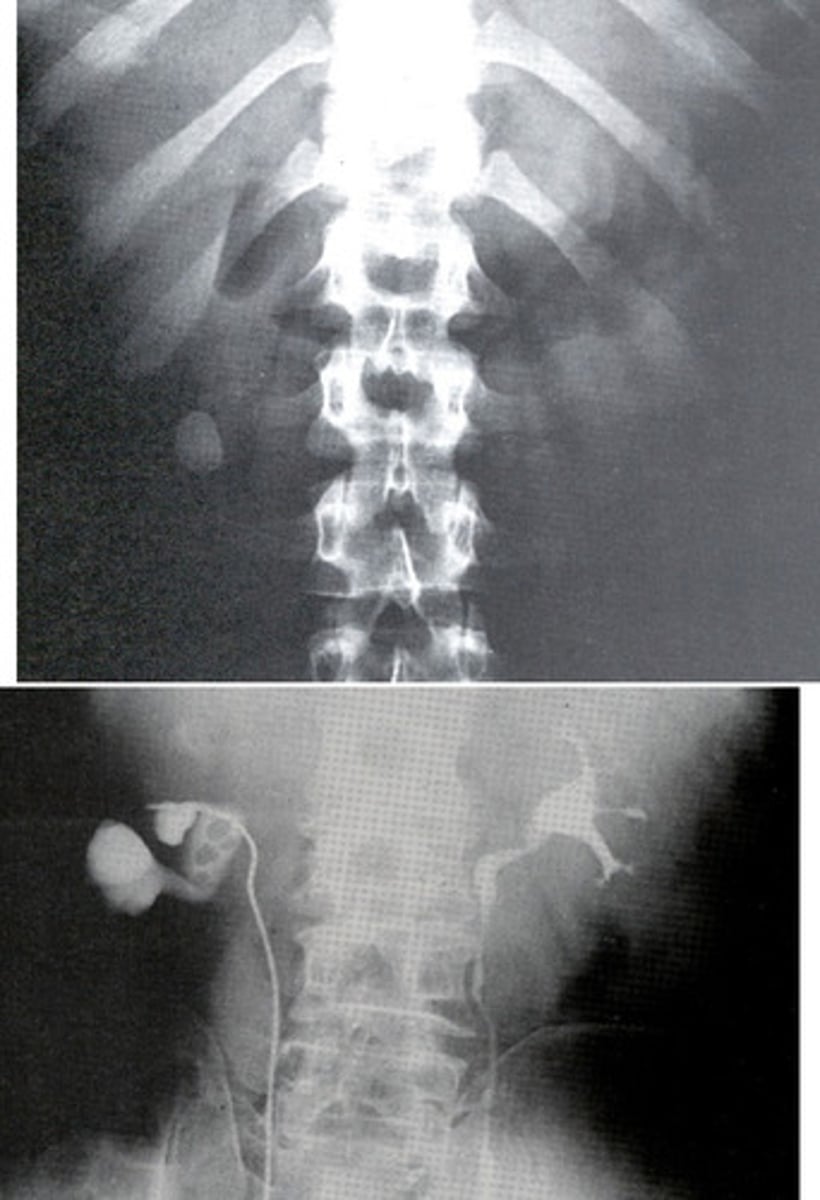

- Renal Agenesis

- Hypertrophic (bigger)

- 2

- What congenital anomaly is the absence of one kidney and ureter?

- How does the kidney that is present appear to compensate for the other not being there?

- How many renal arteries are present in the bottom radiograph?